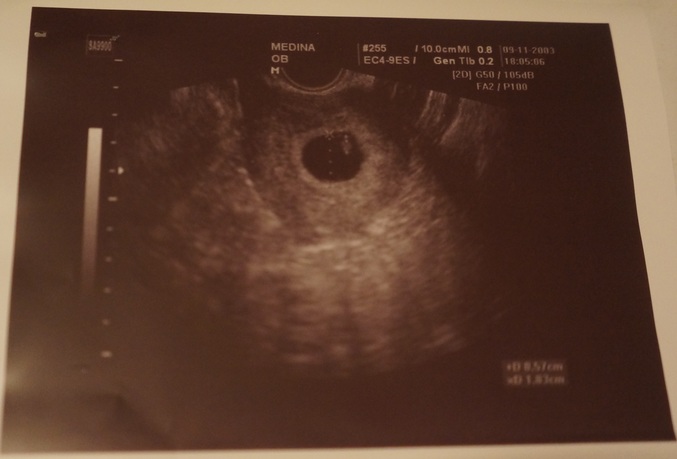

Сегодня была на УЗИ, там уже маленький эмбриончик в 6мм и у него бьется сердечко.

Спасибки! Желаю вам удачи, все будет хорошо. У меня длин.цикл да и О на недельку задержалась, по моим подсчетам и узи у меня 7 акуш.недель, а если считать по М то должно быть 9 акуш.недель, но я то знаю когда все произошло :-)